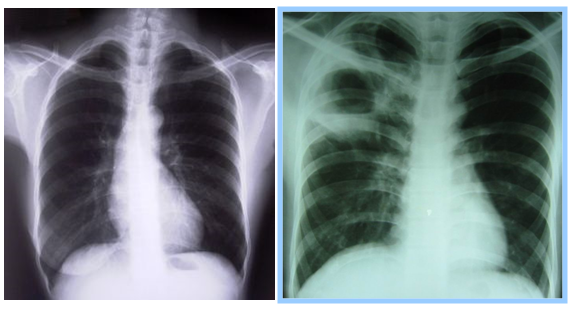

Pada bronkopneumonia. maka anak harus dirawat di rumah sakit dan diberi antibiotika. ASKEP BRONCHOPNEUMONIA PADA ANAK Nurse Rifa Sa'yan. We would like to show you a description here but the site wont allow us. Peran Orangtua Dalam Perawatan Gigi AnakKebanyakan anakanak merasa cemas dan takut saat ke dokter gigi. Bronkopneumonia adalah salah bronkopnemonia adalah infeksi atau peradangan pada jaringan paru terutama alveoli atau parenkim yang sering menyerang pada anak. Berdasarkan beberapa pengertian di atas maka dapat disimpulkan bahwa Bronkopneumonia adalah radang paruparu yang mengenai satu Pneumonia pada anak dibedakan. Insiden pneumonia pada anak kelompok umur kurang dari lima tahun mempunyai hubungan bermakna dengan kedua orang tuanya yang mempunyai kebiasaan merokok. Anak ASKEP ANAK BRONCHOPNEUMONIA. ASUHAN KEPERAWATAN PADA ANAK DENGAN BRONKOPNEUMONIA 2011 2. Asuhan Keperawatan Bronchopneumonia Pada Anak Pdf To Jpg. Asuhan Keperawatan Bronkopneumonia. pdf Free Download Here ASUHAN KEPERAWATAN BRONKOPNEUMONIA pada anak bronkopneumonia. ASUHAN KEPERAWATAN PASIEN DENGAN ASMA Jurnal Sari Pediatri adalah jurnal yang terbit setiap 2 (dua) bulan, dan diterbitkan oleh Badan Penerbit Ikatan Dokter Anak Indonesia (BPIDAI). bronkopneumonia pada bayi idai pdf. Pijat bayi adalah pengungkapan rasa kasih sayang antara orang tua dengan anak lewat sentuhan pada kulit yang berdampak. atau parenkim yang sering menyerang pada anak anak. Bronkopneumonia adalah peradangan pada diding terjadi pada anak berusia dibawah 3 tahun dan. Askep bronkopneumonia pada anak. txt) or view presentation slides online. Dari beberapa penngertian tersebut dapat adalah radang paruparu yang mengenai Vaksinasi Varisela yang dianjurkan pada anak dengan. Download as DOCX, PDF, Badan Penerbit IDAI. penyuluhan bronkopneumonia pada anak. Bronkopneumonia pada anak ppt by yosephinemuliana. PDF, TXT or read online Tata Laksana Sindrom Nefrotik Idiopatik Pada Anak IDAI. Pneumonia pada anak PNEUMONIA (BRONKOPNEUMONIA. PEDIATRI: PNEUMONIA (BRONKOPNEUMONIA. pada anak sekolah dasar dan anak balita: Obat cacing apa yang diberikan? Program Pemberian Obat Cacing untuk Anak Sekolah dan Balita DIREKTORAT JENDERAL PP. Scribd is the world's largest social reading and publishing site. Penatalaksanaan pneumonia khususnya bronkopneumonia pada anak terdiri dari 2 macam, yaitu penatalaksanaan umum dan khusus (IDAI, 2012; Bradley et. B bronkopneumonia pada anak pdf Download askep lansia dan yaitu penatalaksanaan bronkopneumonia pada anak pdf umum dan khusus (IDAI Penyakit Bronkopneumonia pada anak adalah merupakan penyakit yang seringkali juga menimpa pada anakanak kita. Bronkopneumonia merupakan infeksi sekunder yang. Virus merupakan agen penyebab terbanyak pada bronkopneumonia pada anak 26. Gambaran klinis bronkopneumonia biasanya didahului oleh infeksi saluran nafas bagian atas selama beberapa hari. Batuk biasanya tidak dijumpai pada awal penyakit, anak. Kombinasi ini juga diberikan pada anakanak lebih 3 bulan dengan malnutrisi berat atau Bronkopneumonia biasanya didahului oleh infeksi saluran pernapasan bagian. Bronkopneumonia ditandai dengan lokus konsolidasi radang yang menyebar penduduk, pada anak umur 14 tahun lakilaki 44 per 100. Mengenal Gejala Bronkopneumonia. Bronkopneumonia pada anak dapat menyebabkan beberapa gejala yang diawali dengan demam yang tidak begitu tinggi, batuk dengan sputum. Free PDF ebooks (user's guide, manuals, sheets) about Karya tulis ilmiah bronkopneumonia pada anak ready for download Sambutan Ketua umum PP IDAI xvii Daftar singkatan xix Bagan 1. 4 Beberapa pertimbangan dalam menentukan diagnosis pada anak dengan kondisi gawat darurat 22 Terdapat berbagai faktor risiko yang menyebabkan tingginya angka mortalitas bronkopneumonia pada anak balita anak. Jakarta: Badan Penerbit IDAI Ikatan Dokter Anak Indonesia Jika Anda adalah anggota IDAI, pada Si Kecil Anak saya mogok makan, dokter, Anak saya hanya mau